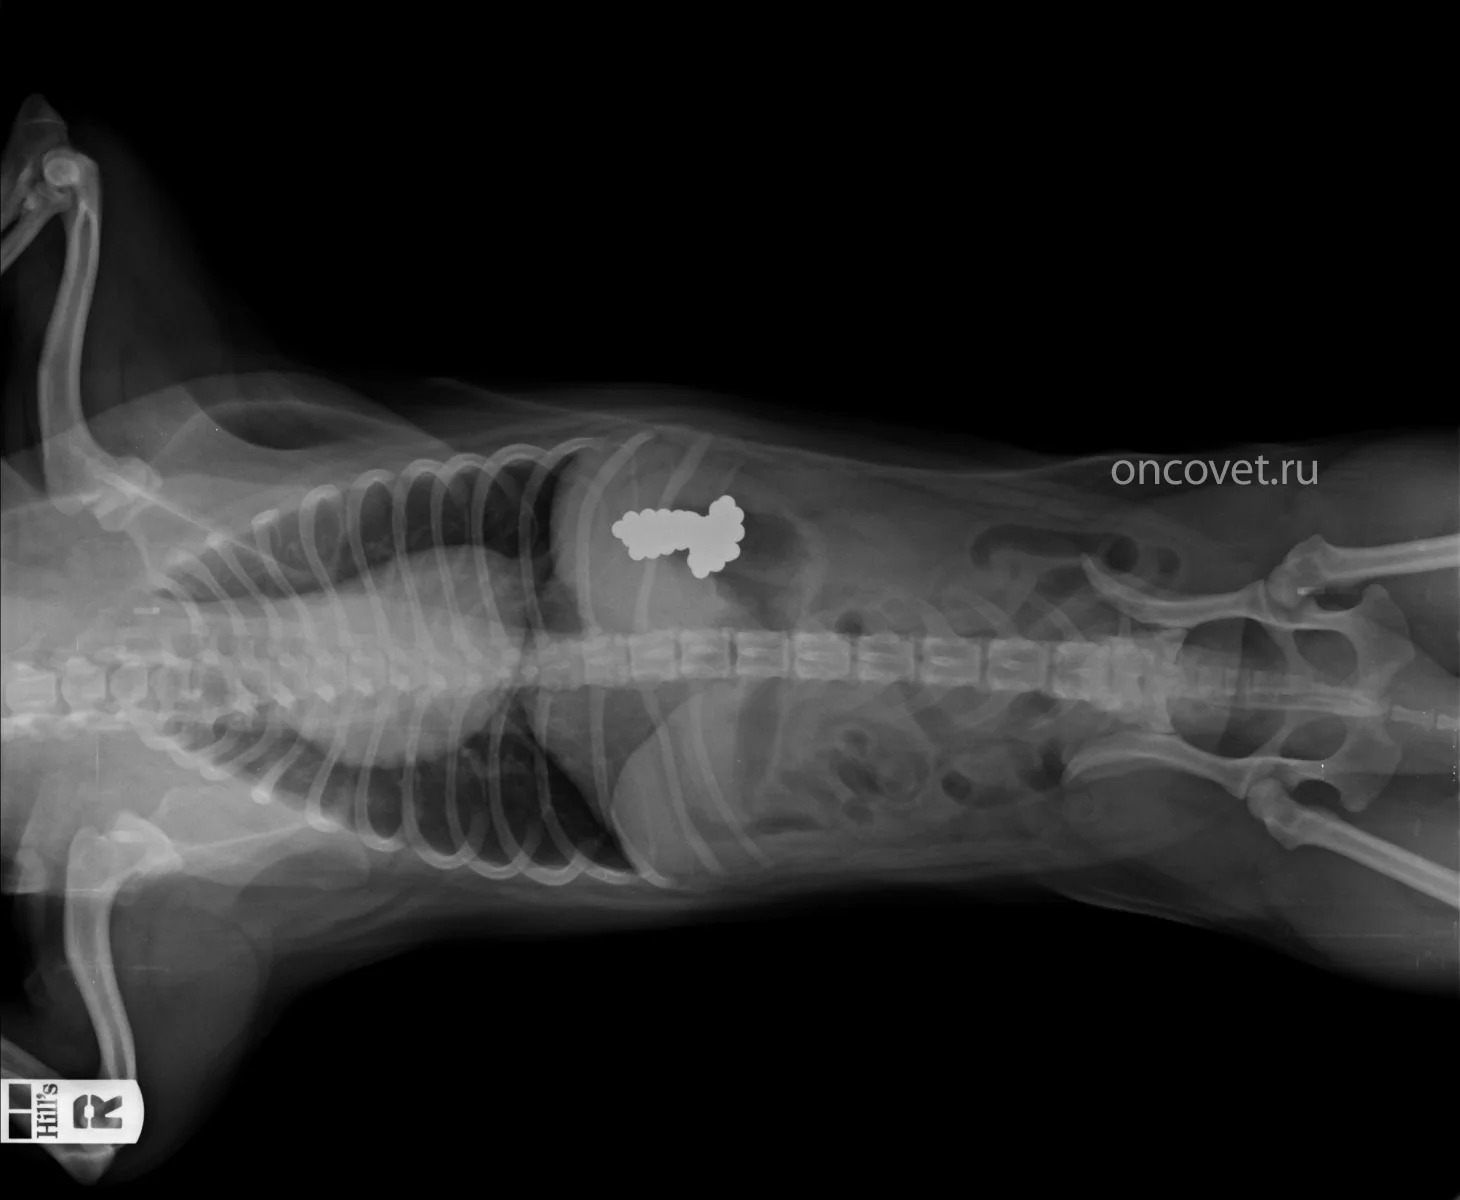

Симптомы и диагностика: Кошки с кишечной непроходимостью могут проявлять такие симптомы, как рвота, отсутствие аппетита, запоры или, наоборот, диарея. Важно отметить, что симптомы могут развиваться быстро, и при подозрении на непроходимость необходимо немедленно обратиться к ветеринару. Диагностика часто включает рентгенографию или ультразвуковое исследование.

Диагностика кишечной непроходимости может осуществляться с помощью различных методов, таких как рентгенография кишечника, ультразвуковое исследование, компьютерная томография и колоноскопия. Кроме того, может быть выполнен анализ кала для выявления бактерий и паразитов.

При подозрении на непроходимость часто назначают рентгенографию с использованием контрастного вещества, такого как сернокислый барий. Эта процедура может помочь выявить инородные тела, однако не все объекты видны на рентгеновских снимках.